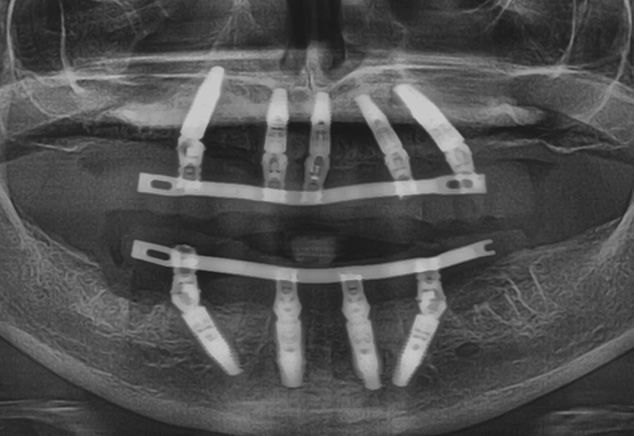

The implant sites were prepared using the manufacturer's protocol (except for bone tapping) for the Straumann BLT implant. The implants were placed using the surgical guide template with the following insertion torques measured: site: #4, #7, #8-9,#11,#13, #21,#23,#26. All torques were >35Ncm with #28 recording 20Ncm insertion torque values. All implants were 4.1mm in diameter and 14mm in length except #7, #8-9, and #11, which were 12mm in length (Fig 7). All 17 and 30 degree-angled implants were bone profiled prior to SRA abutment placement. This allowed the complete seating of the SRA abutment at the recommended 35Ncm torque. Using the available Straumann bone profilers with the appropriate Narrow Connection (NC) or Regular Connection (RC) inserts was a critical step for an abutment to fit correctly. The following SRA abutments (all were 2.5mm gingival heights) were then chosen: straight: #23, #26; 17 degrees: #4, #7, #8-9; and 30 degrees: #11, #13, #21, and #28. Tall protective healing caps were then placed (Fig 8), and the dentures were checked to evaluate that there was adequate space for the pink acrylic to allow for bite registration material thickness. All sockets and buccal gaps to the immediately placed implants were bone grafted. Prior to suturing, the tissue flaps were scalloped with 15c blades to reduce overlap of the flaps over the protective caps. This not only aided in post-operative healing, but also aided in the visualization of the abutments by the restorative dentist for the provisional insertion. The patient was sutured with resorbable 4-0 chromic gut and 5-0 Vicryl™ sutures (Ethicon: Johnson & Johnson) and was released to be seen immediately by Dr. Randel for the coordinated restorative visit. As discussed below, his responsibilities included: bite registration, impressions, and the dental lab conversion of the complete denture to a metal reinforced fixed transitional prosthesis (indirect provisionalization technique). Our team of restorative dentists have been treating full-arch immediately loaded cases on 5-8 implants (depending if restoration is a hybrid or C&B) since 1994. Our earlier experiences, for approximately the first two years (1994-1996), have us all presently using the indirect technique, which in our hands is easier for everyone involved (especially the patient). We handle these coordinated visits between offices, the dental lab, and our Straumann representative weeks prior so we are all on the same page with timing. These coordinated efforts could be compared to a symphony orchestra, where each musician knows their specific part and when and where they are expected to be. Many of our patients have described this fluidity as a seamless experience that they witness first hand and greatly appreciate.

The next afternoon, the prostheses were inserted (Fig 10) and panoramic radiographic confirmation of proper seating was obtained (Fig 11). Any necessary occlusal adjustments were then completed. The patient was then seen every 2-3 weeks for deplaquing and plaque control review per our earlier discussed protocol. The occlusion was also refined as needed. A water irrigation device was given and reviewed at 6 weeks post-surgery.